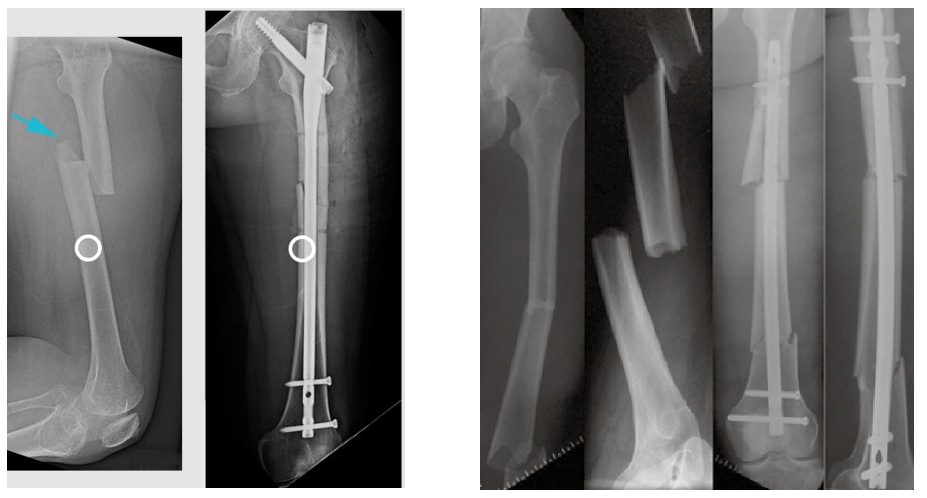

Có thể dùng đinh nội tủy xương đùi như hình sau đây